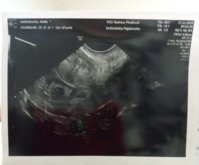

devojki kade na ehoto se merkite zaa tezina na embrionot nemozam da najdam ili golemina da ne znae nekoja od vas da gi cita merkite od ultrazvuk.

eve

Прикачени фајлови:

Од главчето до газето е 4,9 мм.

mi rekoa deka sum 7nedeli i 4 dena a bebeto e 6nedeli i 4dena toa bilo problem ponekogas... inaku bev plodnost oti mnogu krv mi tecese ispaniciv mi rekoa uste ke krvaram imalo malku zgrutcena krv... rekoa kaj nekoi bilo vo red a kaj nekoi ne.. ne prasav progesteronot depo dali da stavam utre pak (mislam na tri dena bese)... inaku utrogestan primam redovno.. doktorkava rece naredna nedela ke se znaelo dali i e vo red ili ne ne bila 100% dali ke bidi se vo red. poludev devojki

Смири се, до 2 недели разлика е во ред. Може да си зачнала покасно. И кај мене 5 дена беше разлика од последна менструација до мерки, ама еве сега 21ва сум и е понапред. Немој да се грижиш. Срценце слушнавте?

se ima be duso srce ko junace 144 cukase imam luge ke vi pratam slika da vidite se ima i pak imam krvarenja taa mi rece nemalo da zastanat imalo mali hematomcinja nemam um vo glava

идни мамички среќна нова и наредна година сите бебиња да сликаме.. ајде мамички давајте помош ми рече докторката во плодност дека немало многу вода односно помало количество на вода... еве ви ги резултатите па се плашам дека навистина нешто не е во ред... примам терапија имав малку повеќе крв без болки без ништо и место не ме држеше морав да одам да видам дали е се во ред и да го слушнам срценцето на ангелчето

ве молам за мислења сега имам ама малку на хартија црвено

еве